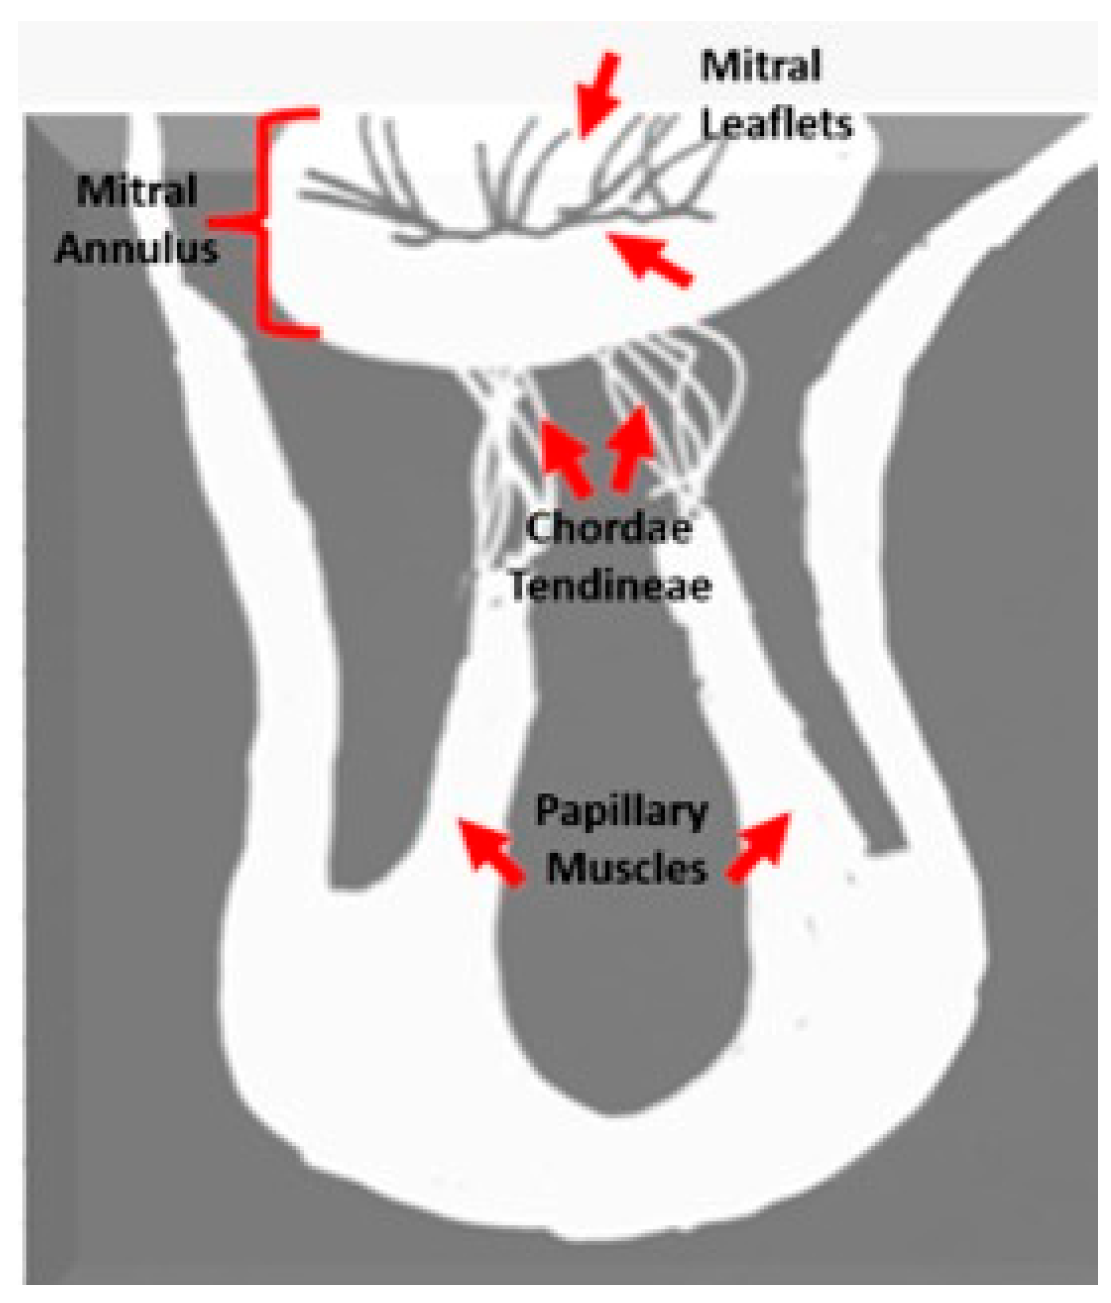

- Koo, H.J.; Yang, D.H.; Oh, S.Y.; Kang, J.-W.; Kim, D.-H.; Song, J.-K.; Lee, J.W.; Chung, C.H.; Lim, T.-H. Demonstration of mitral valve prolapse with CT for planning of mitral valve repair. RadioGraphics 2014, 34, 1537–1552. [Google Scholar] [CrossRef]

- Silva Ferreira, M.V.; Soares, C.S.P.; Araujo-Filho, J.A.B.; Dantas, R.N., Jr.; Torres, R.V.A.; Morais, T.C.; Avila, L.F.R.; Ishikawa, W.; Nomura, C.H.; Rajiah, P.S.; et al. Mitral Annular Disease at Cardiac MRI: What to Know and Look For. RadioGraphics 2024, 44, e230156. [Google Scholar] [CrossRef]